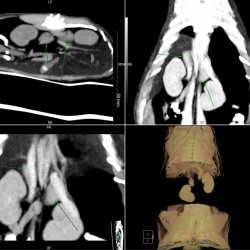

Пациентка 1976 года рождения с жалобами на тянущие боли и парестезии в левой нижней конечности была направлена на МРТ поясничного отдела позвоночника, на которой было выявлено объемное образование...